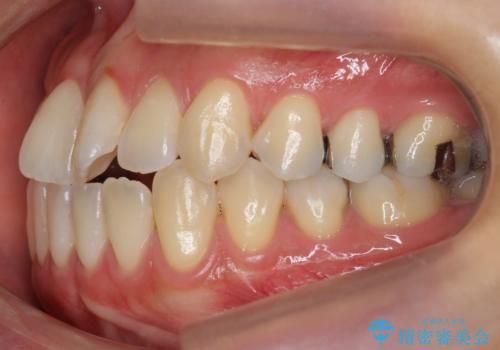

部分矯正コースでしたので左下67の段差は特に治しておりません。

右下567及び左下6の虫歯治療も一緒に行っています。